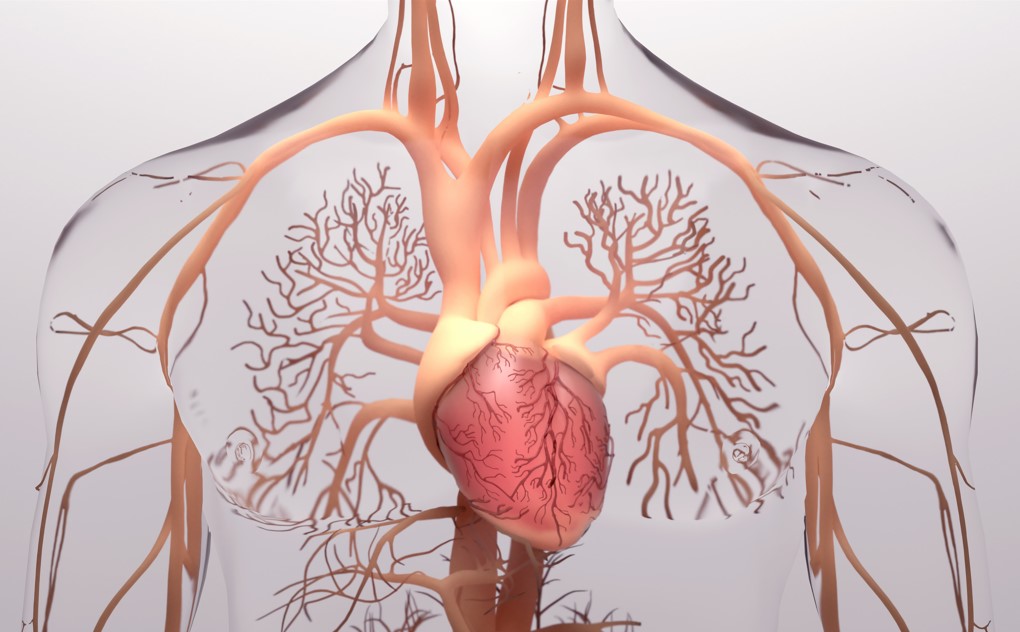

In de circulatie speelt het hart de grootste rol.

Het hart is ongeveer zo groot als een gebalde vuist van de patiënt.

Het hart bestaat uit 4 holle ruimtes

Linkerboezem:

Hier stroomt zuurstofrijk bloed uit de longen naar binnen.

Linkerkamer:

Pompt het zuurstofrijke bloed uit het hele lichaam rond.

Rechterboezem:

Hier stroomt zuurstofarm bloed uit het lichaam.

Rechterkamer:

Pompt het zuurstofarme bloed naar de longen.

Kransslagaders

Dit zijn bloedvaten die aan de buitenkant van de hartspier lopen. Kransslagaders liggen als een soort van krans om de hartspier heen en voeren bloed aan richting het hart.

Er zijn 2 hoofdtakken

Linker Coronair Arterie ( LCA )

Rechter Coronair Arterie ( RCA )

Deze hoofdtakken vertakken zich beide in steeds kleiner wordende vaten. Al deze vaten zorgen er samen voor dat de hartspier voldoende zuurstof en voedingsstoffen krijgt.

4 Hartkleppen

Aortaklep

Tussen de linkerkamer en de aorta

Mitralisklep

Tussen de linkerboezem en linkerkamer

Pulmonalisklep

Tussen rechterkamer en longslagader

Tricuspidalisklep

Tussen rechterboezem en rechterkamer

Kleine bloedsomloop

In de kleine bloedsomloop komt zuurstofarm bloed binnen in de rechterboezem van het hart. De klep tussen de rechterboezem en de rechterkamer opent en het bloed stroomt naar de rechterkamer.

Het hart pompt het bloed via de rechterkamer en de longslagader naar de longen. In de longen geeft het bloed koolzuur af en neemt het zuurstof op. Dit zuurstofrijke bloed stroomt door de longaderen terug naar het hart.

Grote bloedsomloop

De grote bloedsomloop loopt vanuit het hart naar alle delen van het lichaam. De linkerkamer pompt het zuurstofrijke bloed via de aorta het lichaam in. De aorta vertakt zich tot steeds kleinere vaten en haarvaten. De organen gebruiken voedingsstoffen en zuurstof uit de haarvaten en geven hun afvalstoffen af aan de haarvaten. Het zuurstofarme bloed gaat via de aders weer terug naar het hart.